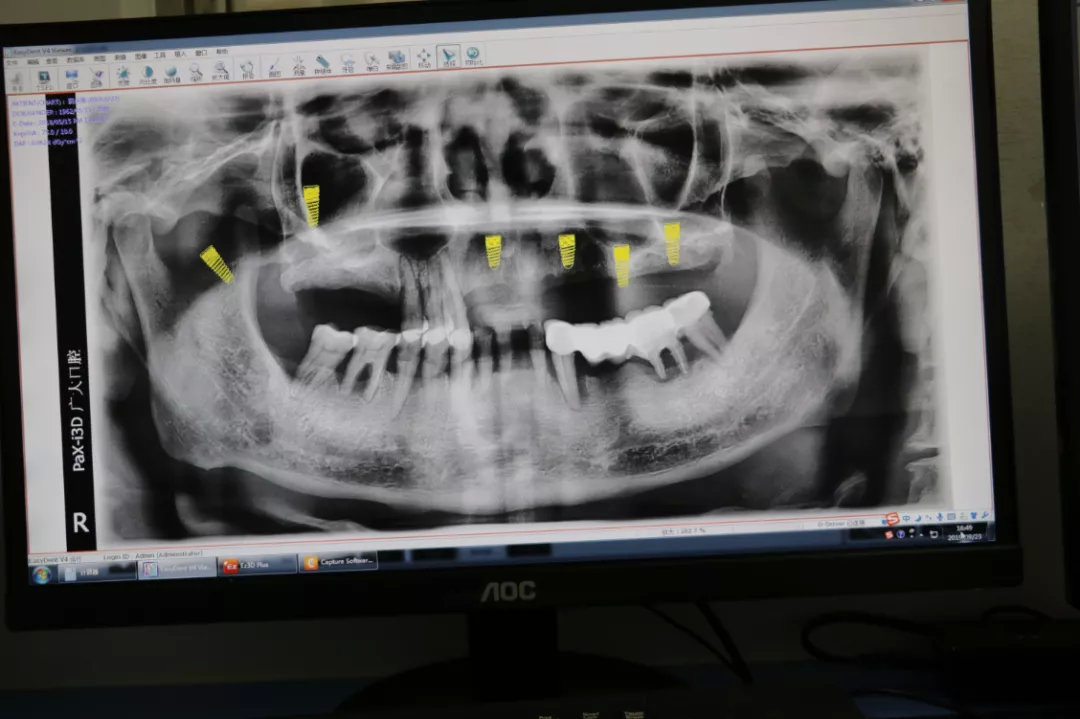

~拍片检查

拍摄颌骨曲面断层全景片、牙片CT

2.种植方案设计

医生根据检查和拍片结果,选择种植体,并提前设计植入数量、位置、方向、长度,让种牙修复更加精准